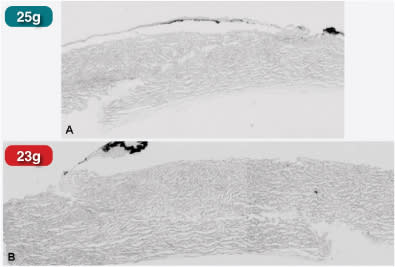

We examined this difference in wound structure in a dynamic fashion using anterior segment spectral-domain OCT and cadaver eyes that allowed for evaluation of wounds immediately after surgery in the setting of varying eye pressures; the result is that, when comparing a 23-g straight incision to a 23-g angled incision, there remains an open straight incision but a closed angled incision, regardless of IOP.

The next part of the experiment involved placing India ink on the wounds to determine where ink particles reach in differently shaped incisions. In a straight incision (Figure 3), even with 25-g cannulas, ink particles are found both in the wound and inside the eye. Conversely, there were no ink particles inside the eye when using an angled incision (Figure 4). As the size of ink particles is comparable to that of bacteria, this is an important finding, and illustrates the importance of an angled incision.

Figure 3. When straight incisions are stained with India ink, ink particles are found inside the wound.

Figure 4. Angled incisions were successful in keeping India ink outside the wound and eye when stain was used.